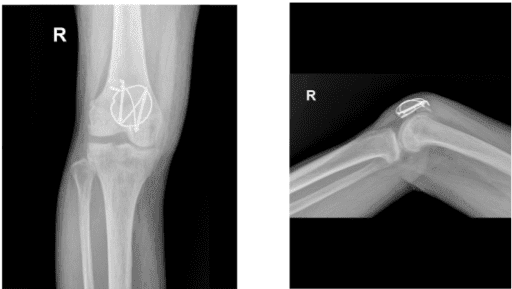

Imagen de rayos X rodilla derecha

La paciente acudió a la consulta para su visita postoperatoria con radiografías de la rodilla derecha. Lleva un inmovilizador de rodilla, niega fiebre y tiene escalofríos. Ella camina con una férula bloqueada en extensión sin ayuda.